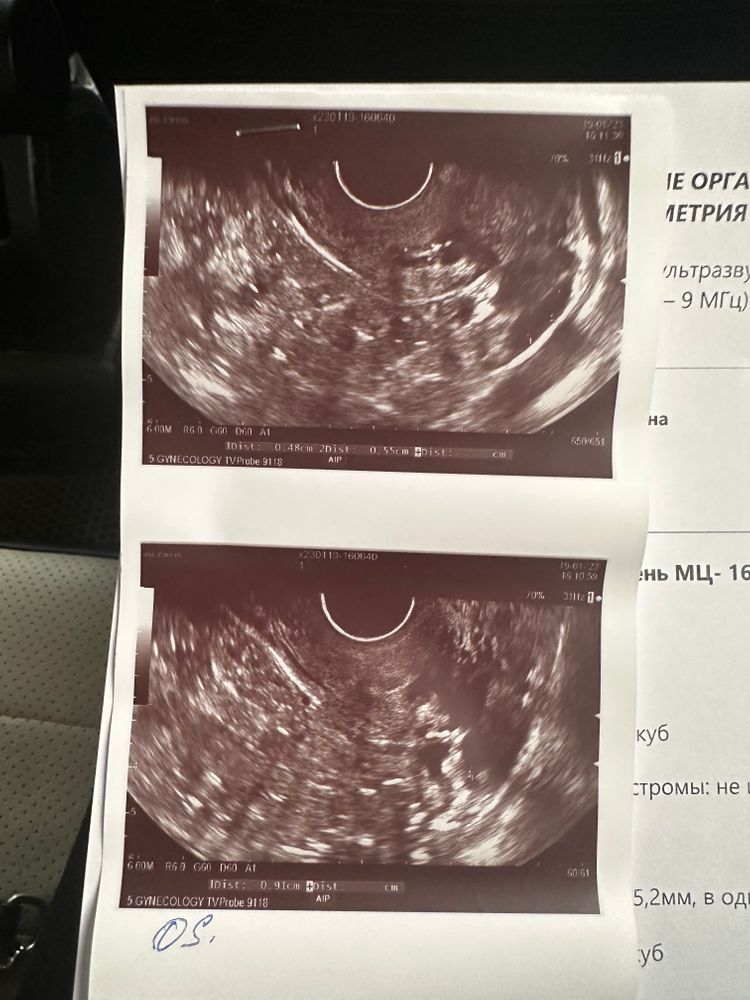

Виктория Виктория в Зачатие 3 года Девочки, оказывается овуляции не произошло…ДФ был, а сегодня его уже нет и желтого тела тоже нет…((( Ждем дня Х (Признаки беременности / Тесты) Посмотрите еще 20 записей на эту тему Отменить Ответить Вероника Так может у вас позже будет ещё овуляция в этом цикле,там вон фолликул 10мм почти… 19.01.2023 Ответить Зима А хгч почему вырос не сказали ? 19.01.2023 Ответить Жду результат 8 дпо Ближе к вечеру тянет немного живот,грудь не болит но тяжелая Чаты Беременных Выберите чат: Январята-2026 Февралята-2026 Мартята-2026 Апрелята-2026 Майчата-2026 Июнята-2026 Июлята-2026 Августята-2026